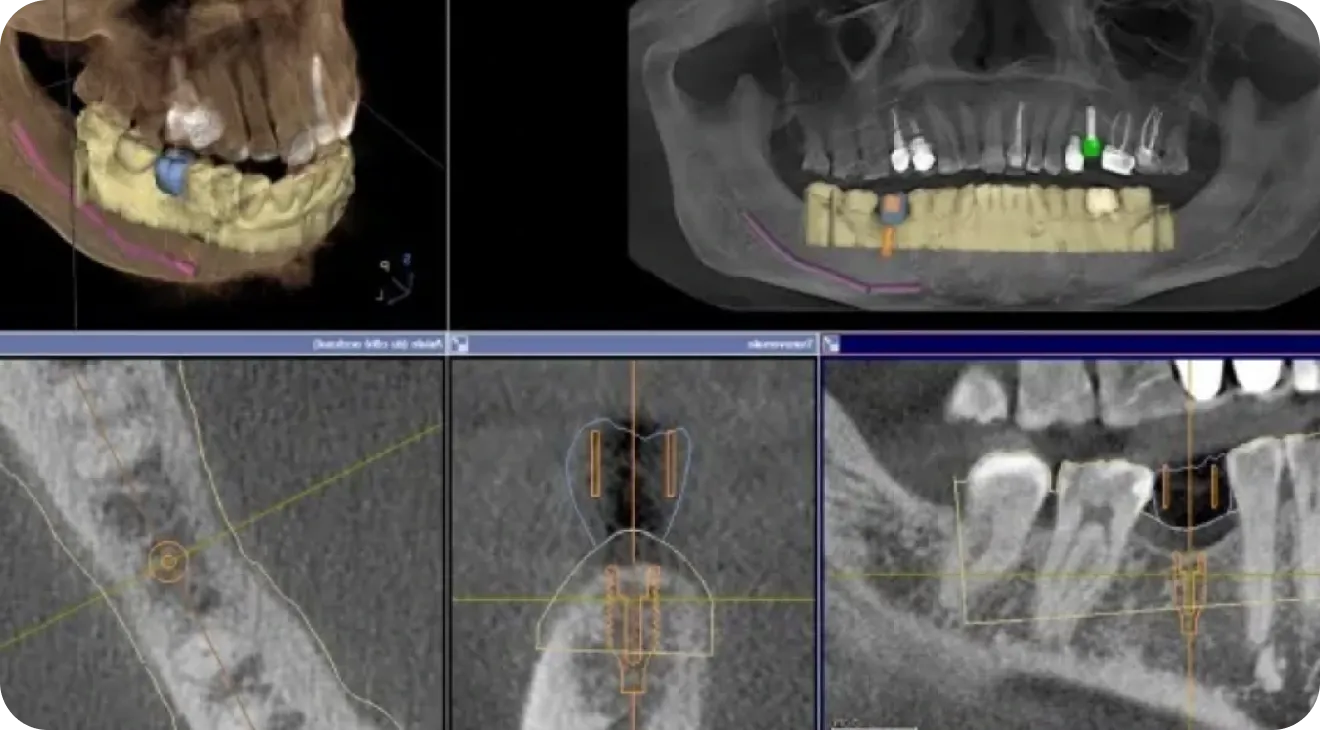

Guide chirurgical

Un système permettant l’impression en 3 dimensions de guides chirurgicaux sur-mesure afin de permettre au praticien de pouvoir planifier avec précision les opérations.